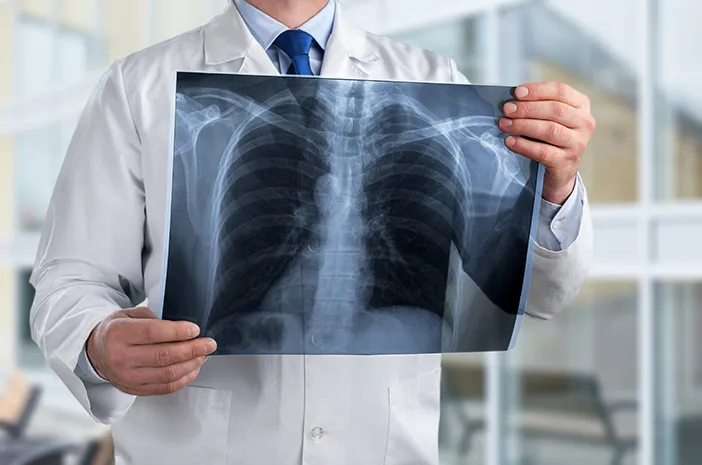

Panduan Pemeriksaan Foto Rontgen Thorax

• Membawa lembar permintaan pemeriksaan radiologi dari dokter dan kartu identitas

• Jika sedang hamil mohon untuk lapor ke petugas sebelum dilakukan pemeriksaan

• Lepas perhiasan dan benda berbahan logam lainnya

• Kenakan pakaian yang mudah dilepas atau memakai pakaian ganti yang disediakan

• Instruksi pemeriksaan tahan nafas sejenak dan tidak bergerak saat pengambilan gambar

Rontgen Thorax

Biaya Pemeriksaan Foto Rontgen Thorax AP (Antero Posterior)/PA (Postero Anterior)

Rp 105.000